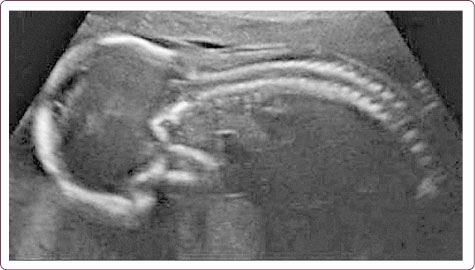

Ведь когда-то мы лежали в утробе матери, свернувшись в первичный изгиб зародыша (рис. 18). Вот так с возрастом мы снова возвращаемся к себе, к своим истокам, оправдывая поговорку: «Что стар, что млад» (рис. 19).

Рис. 18. Зародыш в утробе матери

Рис. 19. Старушка